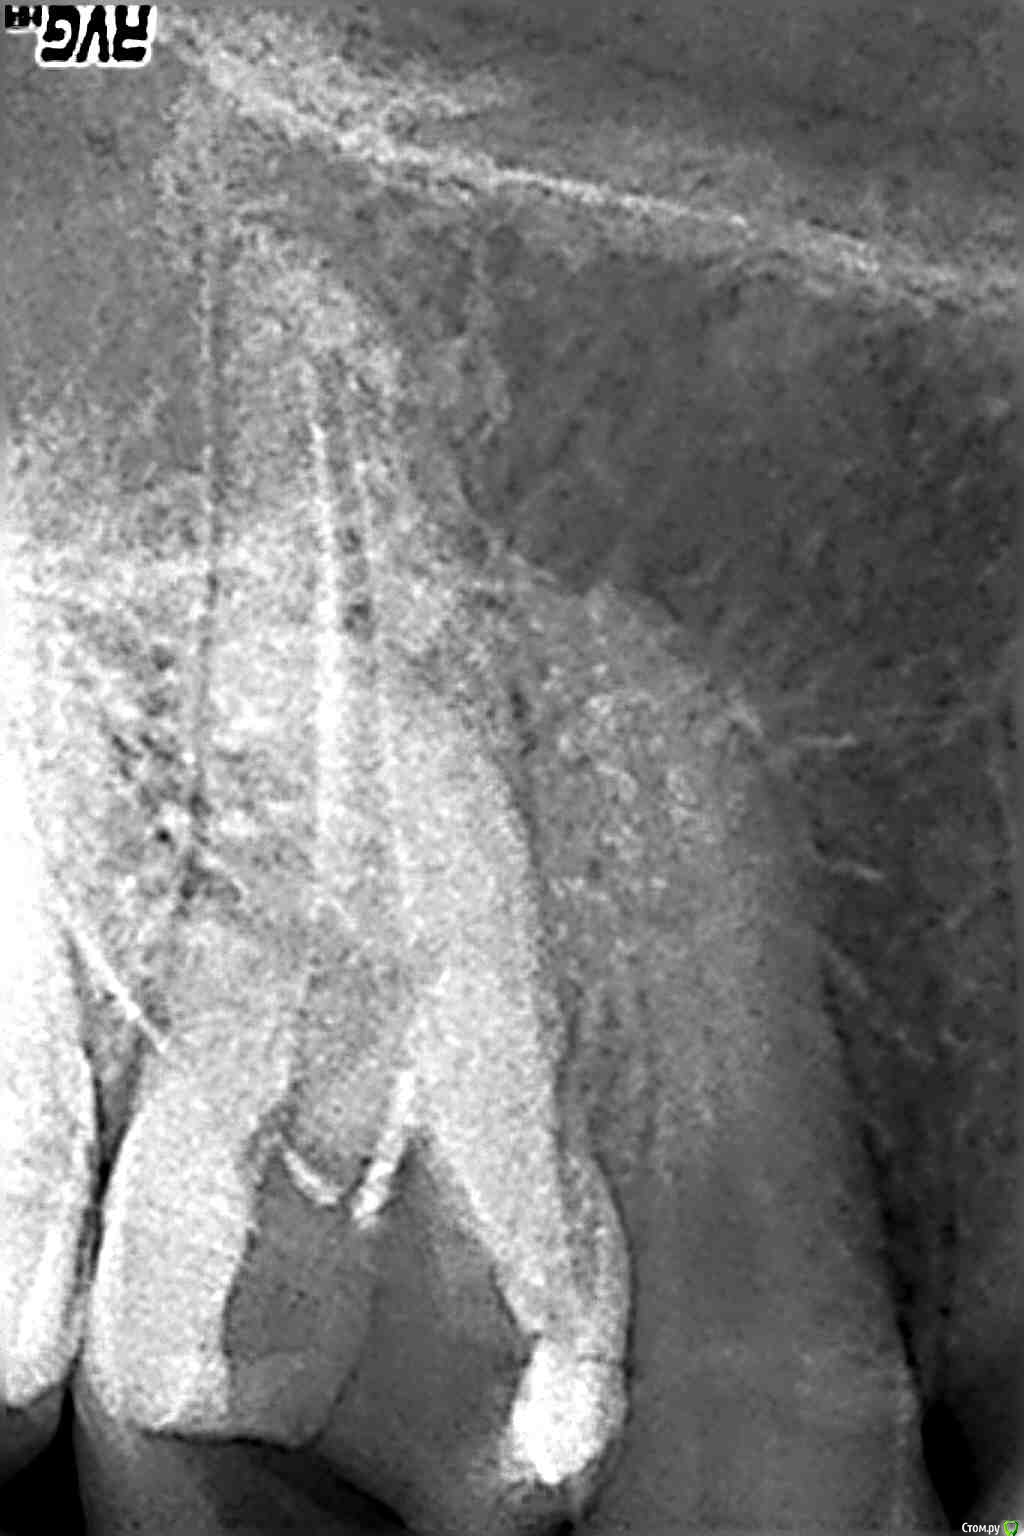

bozz903 Опубликовано 19 декабря, 2015 Поделиться Опубликовано 19 декабря, 2015 Ныл периодически 16-ый зуб в течении 3-х лет. Месяц назад пошел к врачу. Прочистили каналы, положили лекарство на несколько дней, потом гуттаперча и пломбировка. Вчера выпил немного холодного молока и зуб начал ныть. Не до конца прочистили каналы? Ссылка на комментарий

bozz903 Опубликовано 24 декабря, 2015 Автор Поделиться Опубликовано 24 декабря, 2015 (изменено) Месяц назад у меня как раз обострился периодонтит от холодного арбуза, я думаю что возможно какой-то канал так до конца мне и не прочистили. Вииду того, что стоимость лечения равнялась половине средней з/п в нашем регионе, хотелось бы убедится как-то в качестве лечения пока не прошло много времени, тем более насторожили неоднократные попытки врача "получить контакт" апекс-локатором перед наложением гуттаперчи. И да, на мои жалобы о непрекращающейся боли врач хотел заняться 15 зубом. Изменено 24 декабря, 2015 пользователем bozz903 Ссылка на комментарий

bozz903 Опубликовано 19 марта, 2016 Автор Поделиться Опубликовано 19 марта, 2016 Здравствуйте. С наступлением весны все тот же 16 зуб стал реагировать на температуру очень сильно. Также ноет сам по себе периодически. Боль не похожа на гиперчувствительность эмали.Сделал новые снимки. Что нибудь можно сказать по сравнение с теми, которые прикреплены в первом моем сообщении? Ссылка на комментарий